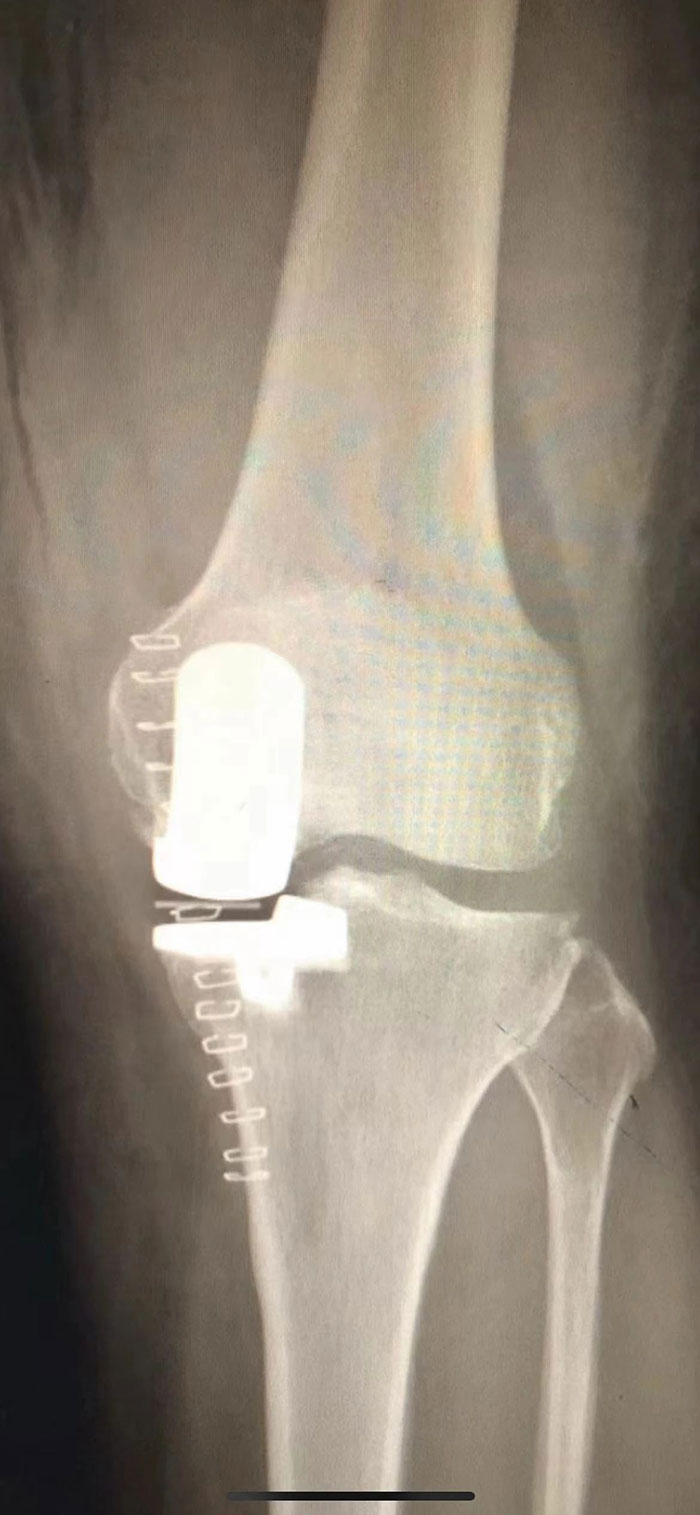

近日,滄州市中心醫(yī)院關節(jié)外三科(骨六科)成功為一名左膝關節(jié)前內側關節(jié)炎高齡患者完成左膝關節(jié)單髁保膝術。

張磊主任經過仔細地了解病史、檢查發(fā)現,王大娘左側膝關節(jié)退變,關節(jié)面磨損嚴重,且股骨內側髁有骨壞死,疼痛明顯。“以患者目前的情況來看,左膝關節(jié)內側關節(jié)面磨損嚴重,癥狀也是以內側為主,診斷為左膝關節(jié)前內側關節(jié)炎,可行左膝關節(jié)單髁保膝手術,改善疼痛,恢復行走能力?!痹谂c患者及其家屬詳細溝通后,經討論,張磊決定為其實施左膝關節(jié)單髁保膝手術,盡全力為王大娘保留膝關節(jié)的同時解除病痛的折磨。聽到這個消息后,王大娘的眼里又重新燃起了希望。

一個單髁保膝手術要想達到理想的手術治療效果并不簡單,這與假體的大小、方向和松緊度密切相關,其中任何一點出現差池,結果都會差強人意。為此,關節(jié)外三科(骨六科)團隊在術前和術中進行了精確的設計和測量,制定周密詳盡的手術方案。

手術當天,在麻醉科醫(yī)生的配合下,關節(jié)外三科(骨六科)團隊為王大娘實施了左膝關節(jié)單髁保膝手術,一招解決了膝關節(jié)疼痛煩惱。

術后第二天,王大娘左膝疼痛好轉。在醫(yī)護人員的指導下,王大娘借助助步器下地行走。看著自己逐漸靈便的雙腿、感受著自己新生的膝關節(jié),王大娘滿心歡喜道:“謝謝你們,讓我再次體會到行走的快樂,給我左腿又注入了新的活力!”

張磊主任介紹說:保膝治療是保留膝關節(jié)大部分結構不被破壞,可以恢復膝關節(jié)正常功能,患者術后感覺與正常膝關節(jié)一樣,極大的提高老年患者的生活質量。